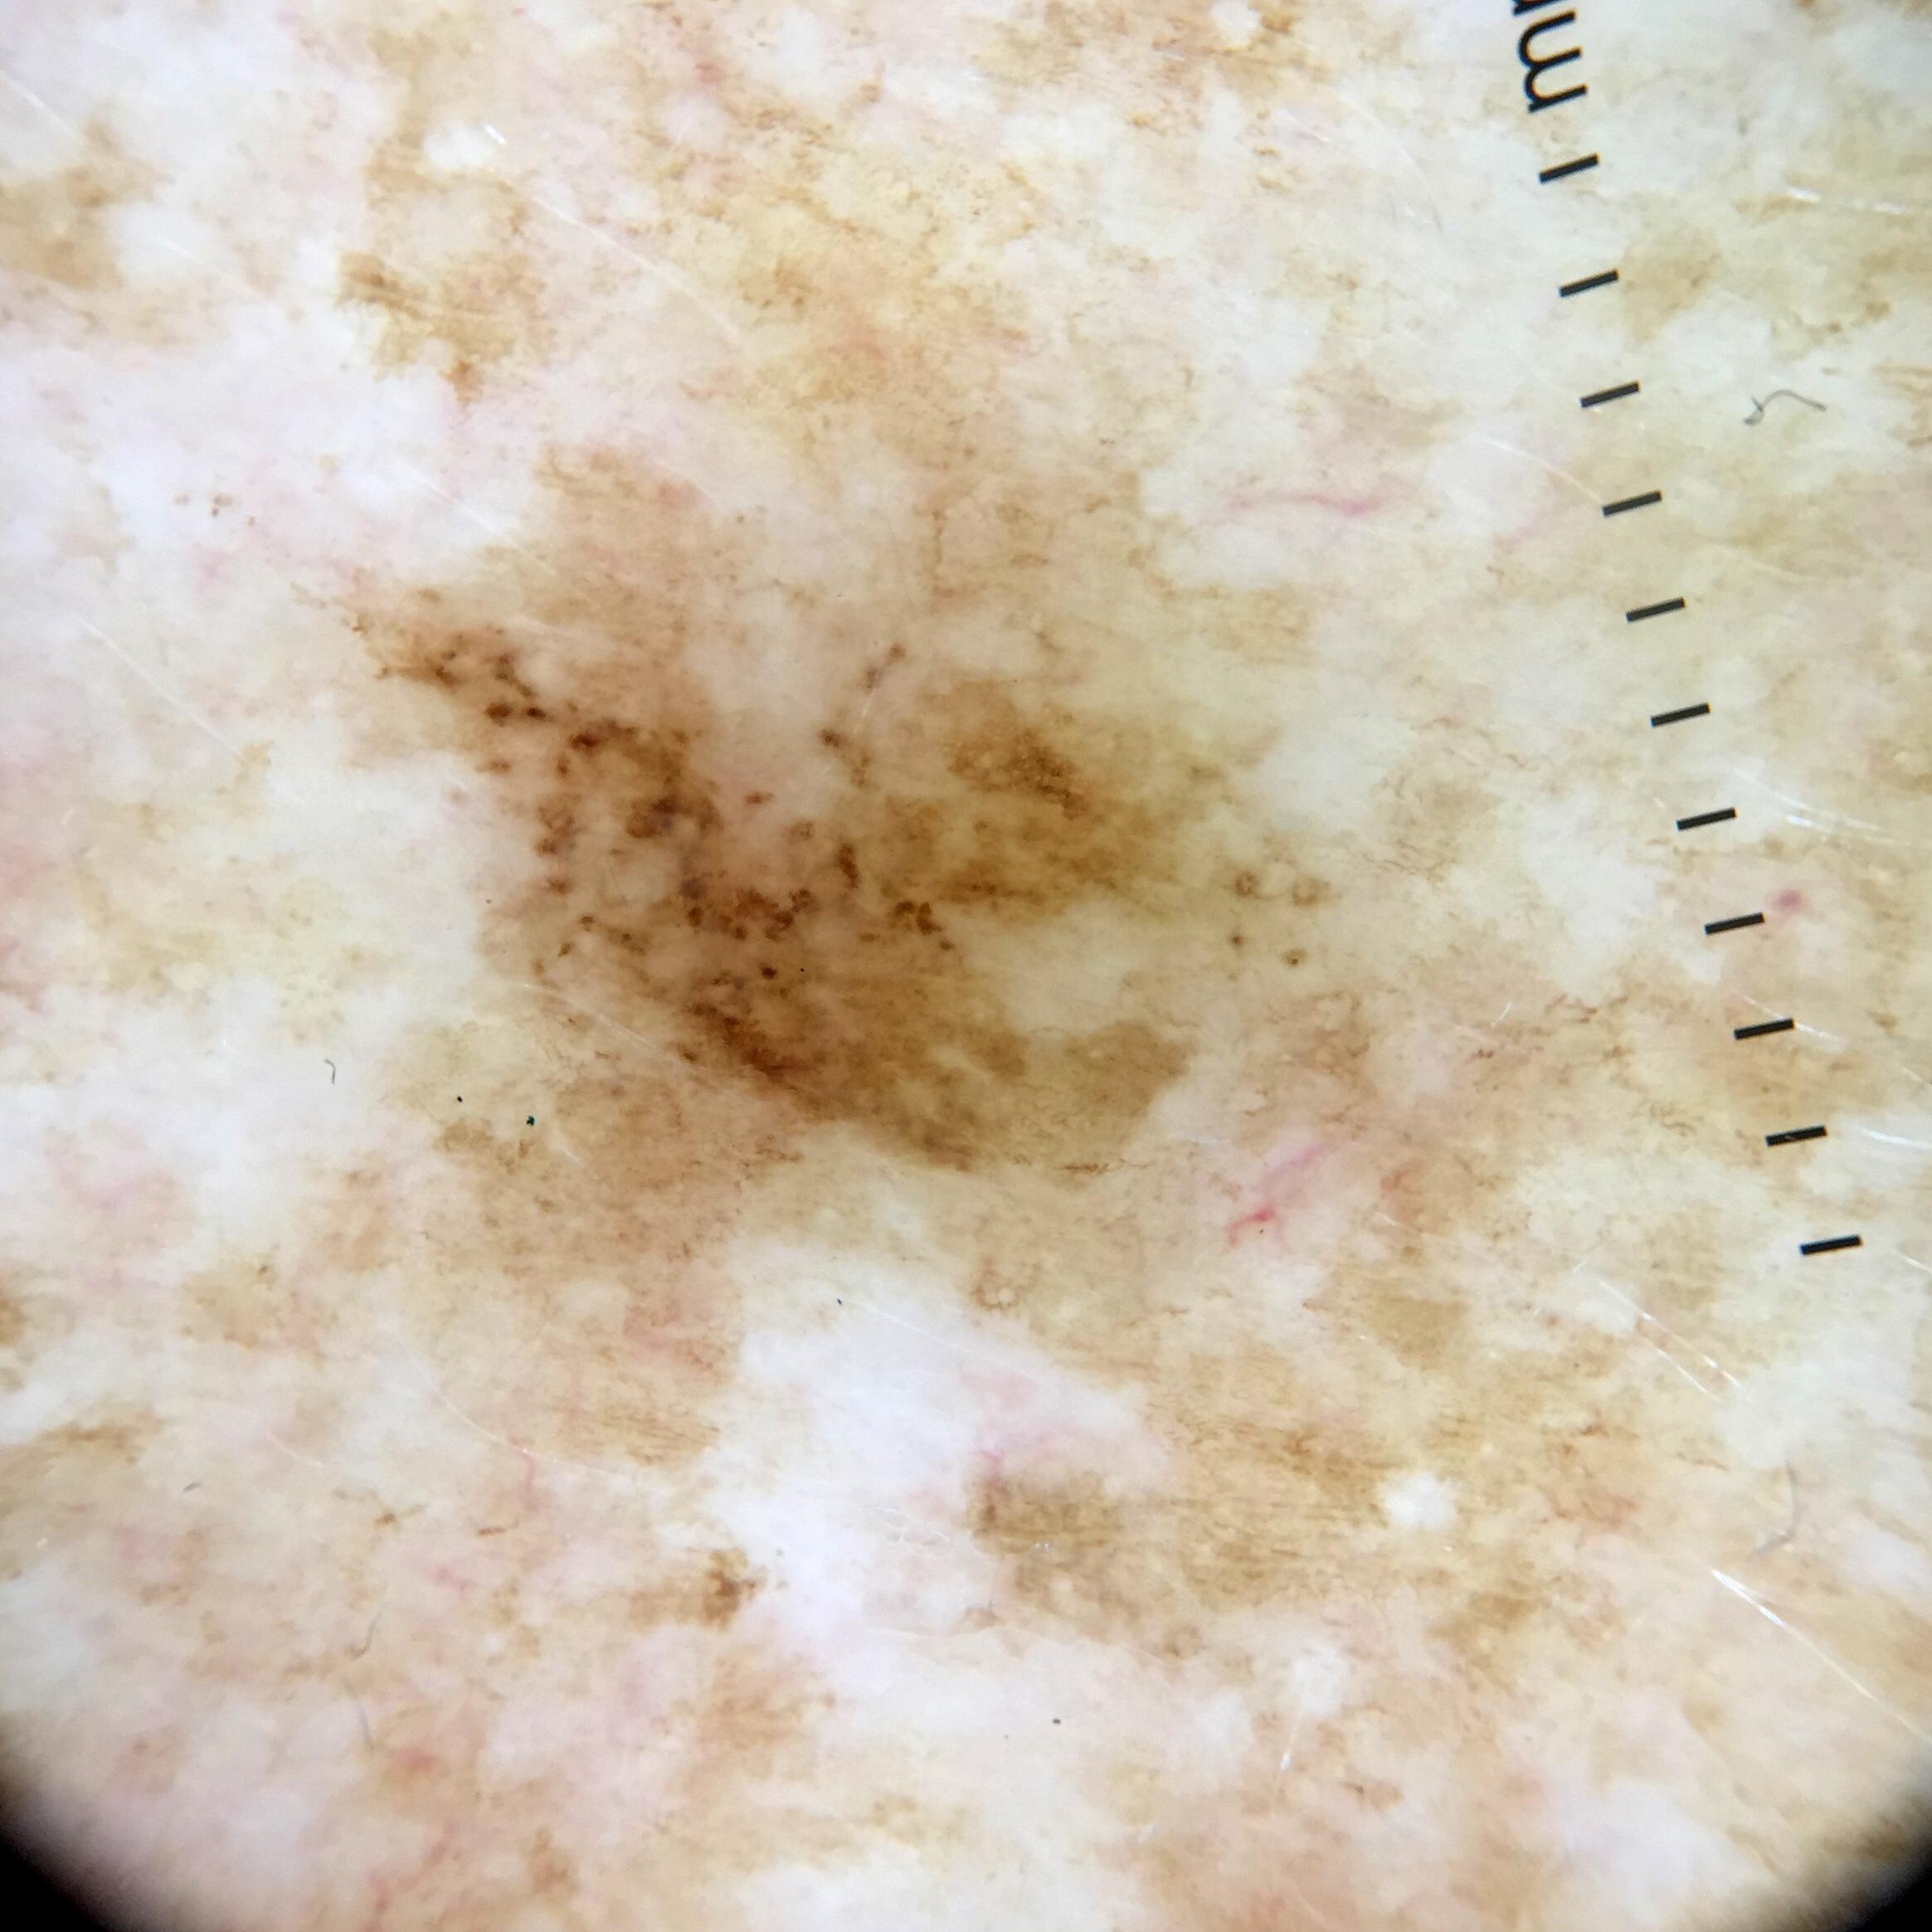

{

"age_approx": 65,

"anatom_site_general": "upper extremity",

"concomitant_biopsy": false,

"diagnosis_1": "Benign",

"diagnosis_confirm_type": "serial imaging showing no change",

"fitzpatrick_skin_type": "II",

"image_type": "dermoscopic",

"lesion_id": "IL_9283481",

"patient_id": "IP_6326286",

"sex": "female"

}